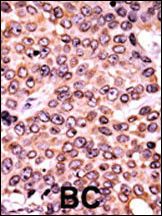

WB: 1:1000

IHC-P: 1:50~100

DB: 1:500